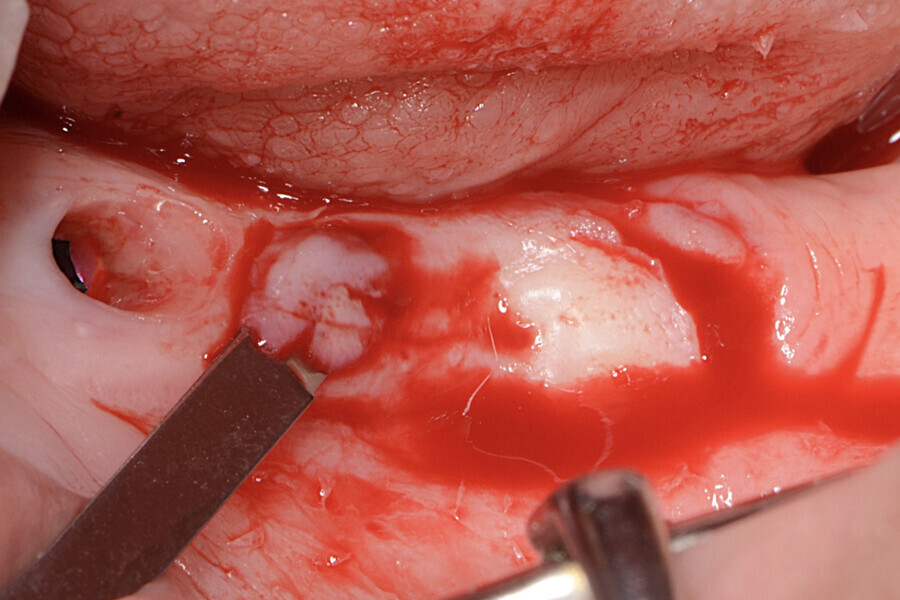

La zone opératoire a été anesthésiée avec de l’articaïne et de l’épinéphrine à 1:100 000. Le site receveur a été incisé au moyen d’un scalpel tranchant, afin de créer un lit périosté libre de toute attache musculaire. Deux incisions crestales parallèles ont été effectuées au niveau de la région distale des implants avec une lame n° 15C, et reliées par une incision horizontale (Figs. 2 à 5).

Le prolongement des incisions vers la région crestale et la distance qui les sépare, dépendent du volume de la greffe de tissu kératinisé nécessaire pour chaque cas. La désépithélialisation du lambeau a été effectuée à l’aide d’une lame n° 15C (Fig. 6), et un lambeau d’épaisseur partielle a été élevé (Fig. 7). Le lambeau a été décollé par une incision superficielle interne de la partie apicale, afin d’en permettre le déplacement passif et la suture sans tension. Le lambeau a alors été déplacé en direction mésiale avec une rotation de 180° (Figs. 8 et 9).